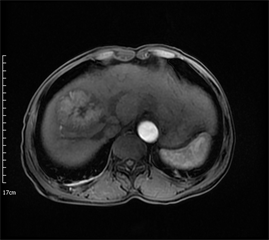

Figure 2. Axial MRI images of the same patient as in Figure 1 after TACE treatment. (a) T1-weighted unenhanced image shows a hypointensive lesion in right lobe of liver. (b) Arterial phase contrast-enhanced image shows the central necrotic area and peripheral enhanced area in the lesion. (c) ADC map. (d) Dslow map. (e) Dfast map. (f) f map.